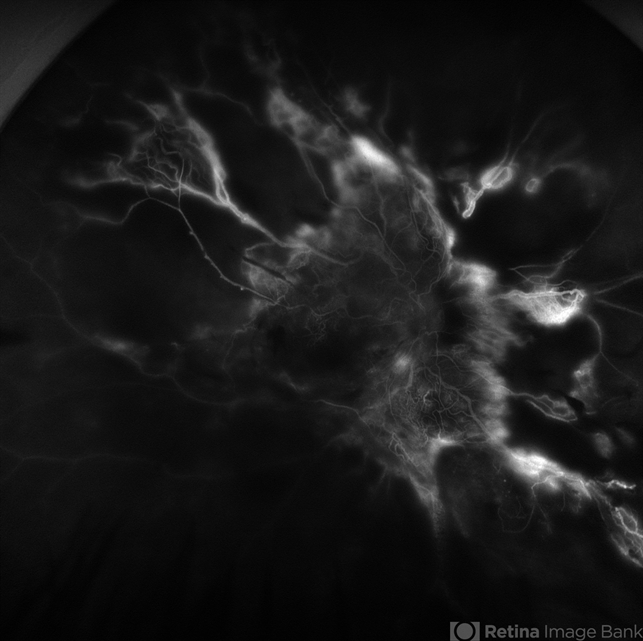

Severe Proliferative Diabetic Retinopathy

Severe PDR

diabetic blindness, proliferative diabetic retinopathy (PDR), fibrovascular proliferation, tractional retinal detachment, nonperfusion diabetic retinopathy, peripheral retinal nonperfusion

33 year old female with 1 month history of vision loss right eye. Severe PDR was noted with VH and a TRD with severe FVP present OD.